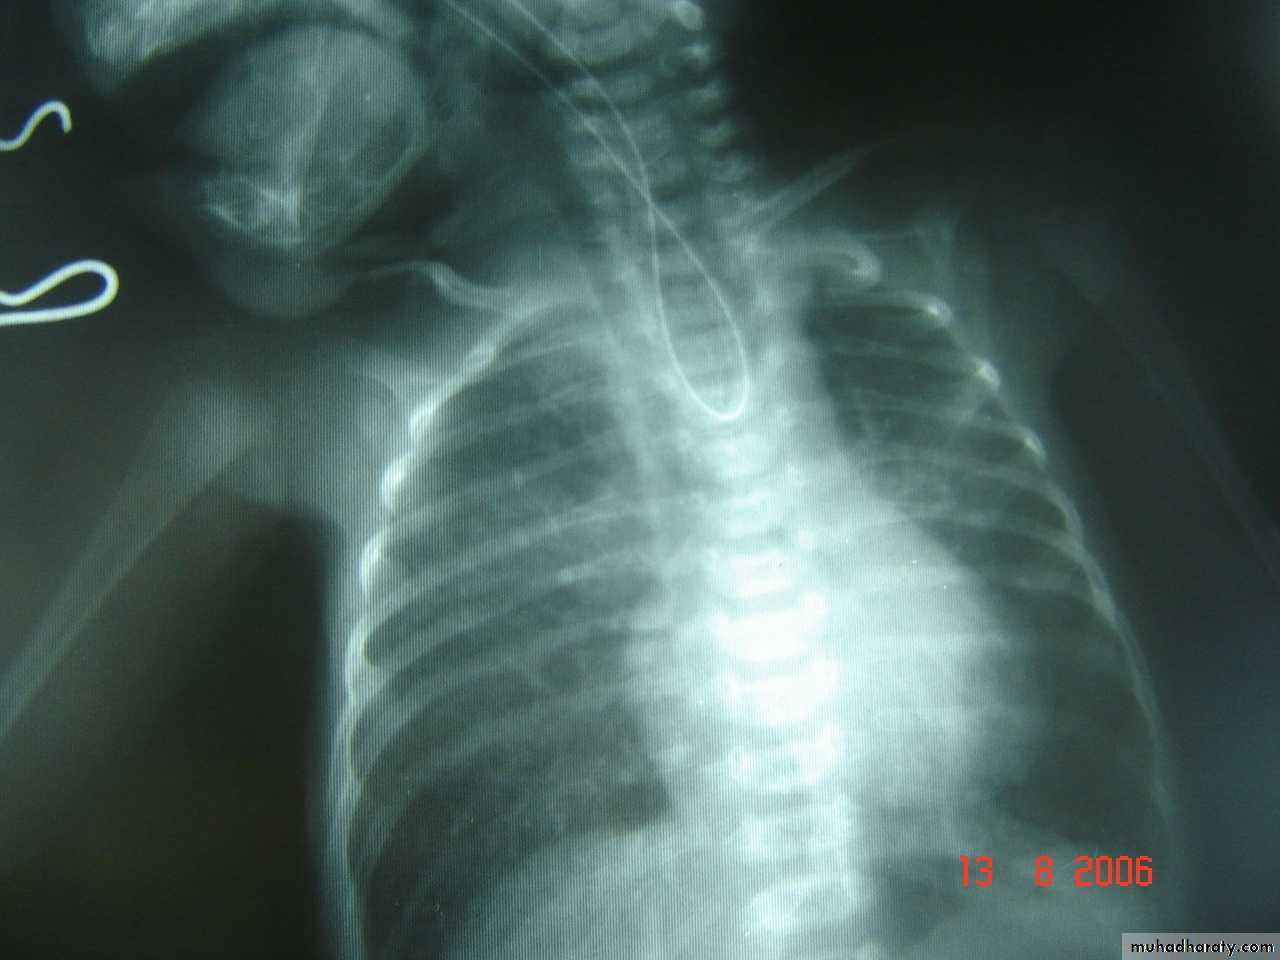

Oesophageal Atresia and Tracheo-Oesophageal Fistula,